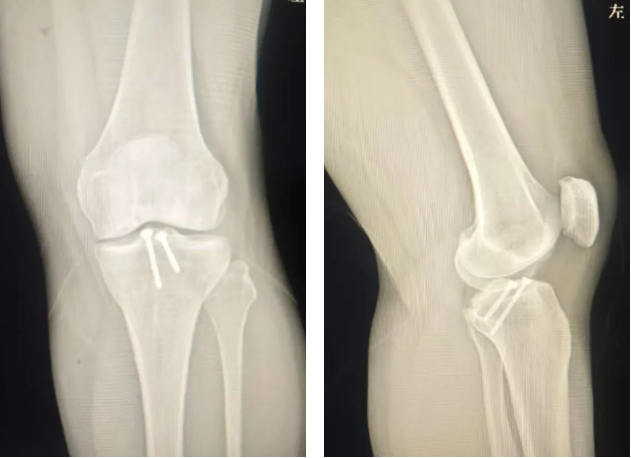

术前X线检查